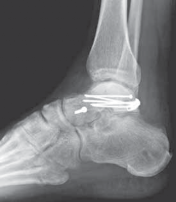

Finally, countersunk, interfragmentary small fragment (3.5 mm) screws or mini-plate and screw constructs are used to fix the talar neck fracture ( TECH FIG 3).

TECHNIQUES D E F TECH FIG 3 •

D. Postoperative fixation of talar body fracture requiring medial malleolar osteotomy. E. Postoperative lateral view of talar body fracture. F. Postoperative Canale view of talus. OPEN REDUCTION AND INTERNAL FIXATION OF THE POSTERIOR BODY OF THE TALUS